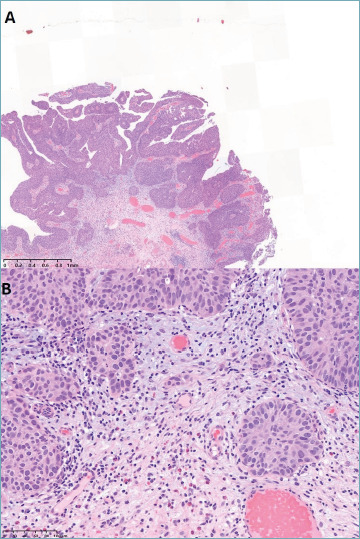

According to the current WHO classification, urothelial tumors consist of non-invasive urothelial neoplasms and invasive urothelial carcinoma which is supposed to include all tumors with invasion regardless of extent and pattern. Some pathologists are uncomfortable about such all-inclusive definition of invasive urothelial carcinoma and it is questionable whether invasiveness is a valid defining feature for primary distinction of urothelial tumors. Considering that most pathologists understand urothelial tumors based on the dual-track pathway model, we would like to raise concern that it may be necessary to rethink the validity of the current WHO classification compared to the restructuring into papillary vs non-papillary tumors. In our opinion, such restructuring would align the WHO classification with the pathogenesis model and could clarify the diagnostic terminology regarding invasiveness. The term of urothelial carcinoma in situ may also be reconsidered.

Abstract Image